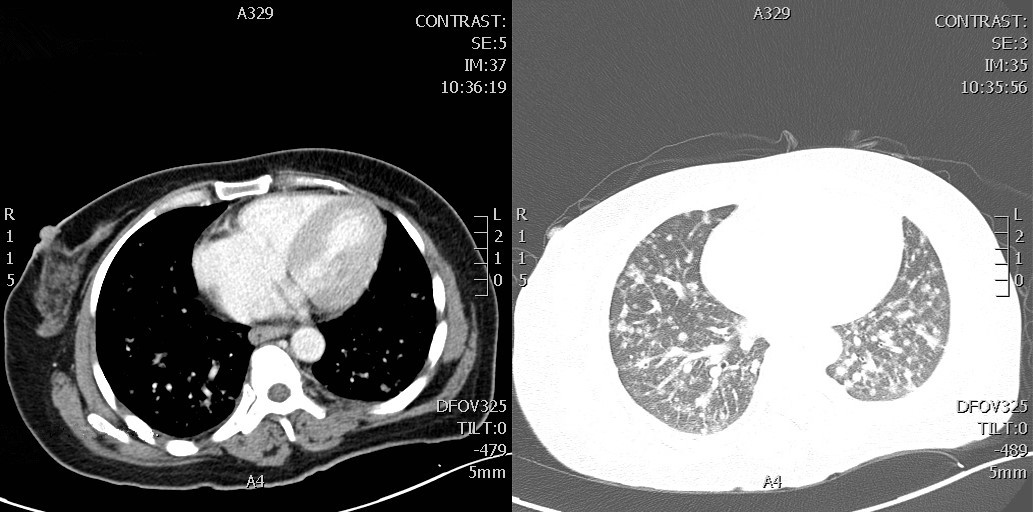

Moreover, the routine chest X-rays revealed scattered, diffuse shadows in both bilateral lungs, while a contrast-enhanced chest computed tomography (CT) scan revealed pulmonary nodules at the apex of the left lung, consistent with lung cancer with multiple double- pulmonary metastases (Figure 3). In the serum tumor markers, the carcinoembryonic antigen is elevated to 19.19 ng/ml, and the carbohydrate antigen 153 is elevated to 69.99 U/ml. Positron emission tomography-CT (PET-CT), a more sensitive tool for detecting meningeal dissemination, confirmed diffuse malignant lesions in the lung, with suspected lymphatic metastasis involving the left supraclavicular, inferior thoracic, and mediastinal lymph nodes. No abnormalities were found in other regions (Figure 4). A biopsy of the left supraclavicular lymph nodes revealed invasive adenocarcinoma cells (Figure 5).

Figure 3 Enhanced computed tomography (CT) scan of the chest

The CT scan detected pulmonary nodules in the apex of the left lung.